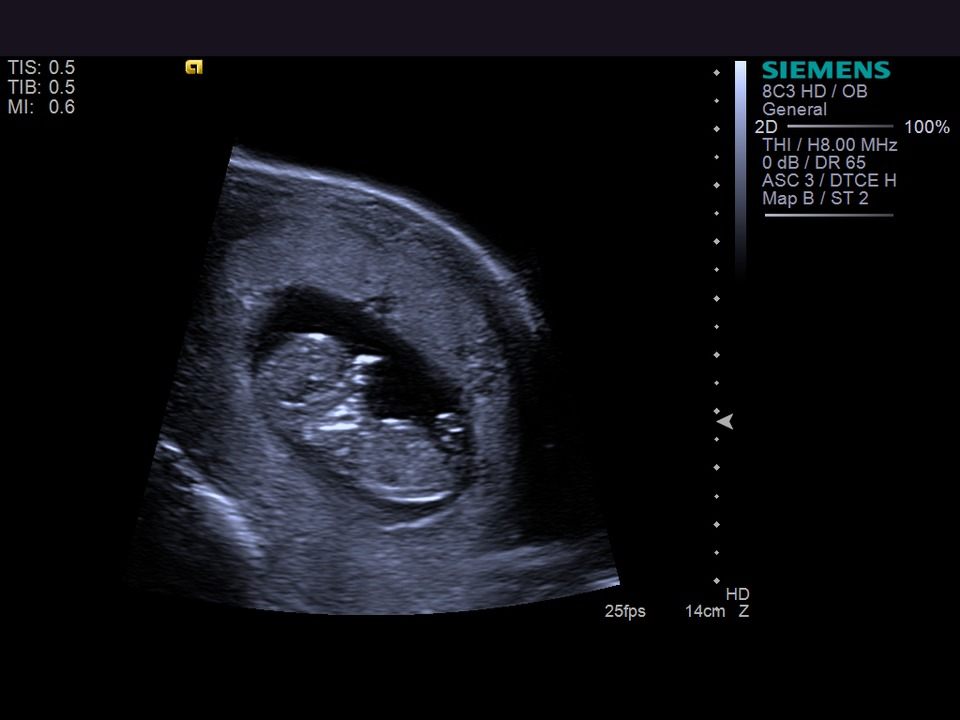

УЗИ Машеньке 9-10 недель.

10 неделя беременности. Развитие плода. УЗИ в 3D. Как выглядит ребенок на 10 неделе